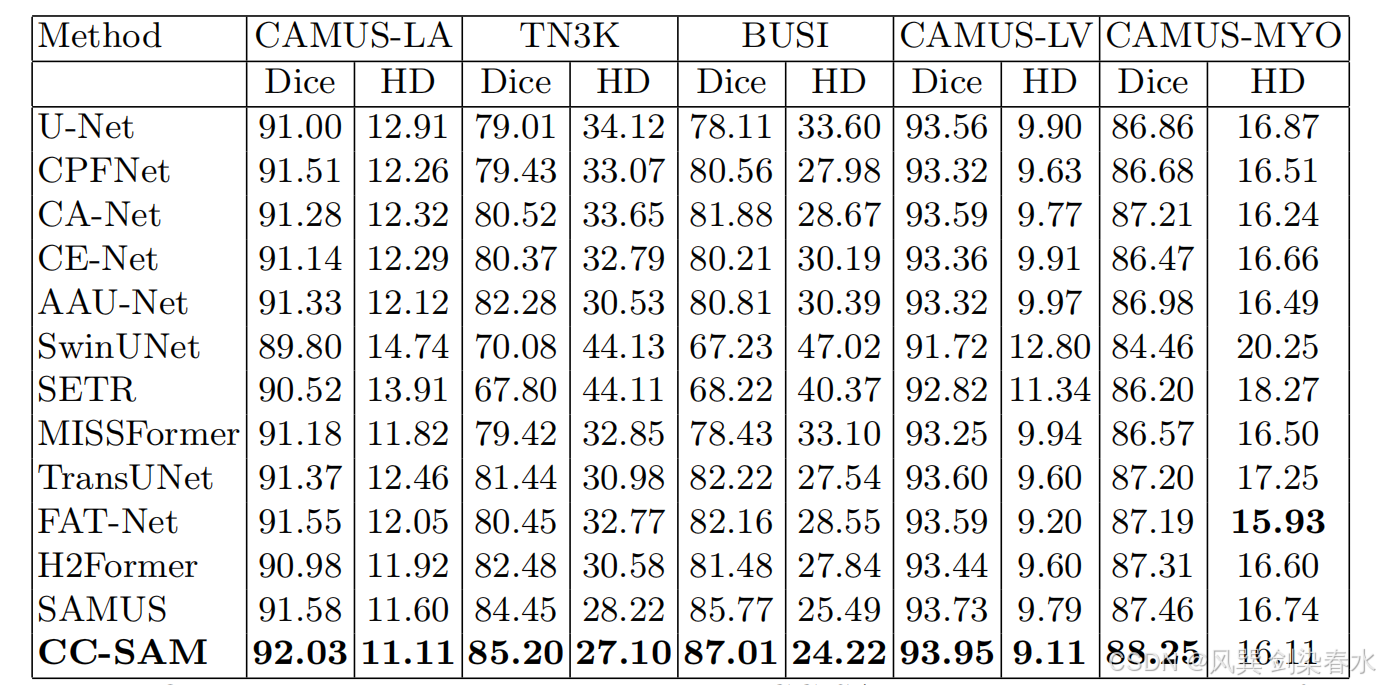

本文考虑了两种场景来与遵循 SAMUS 的最先进的模型进行比较。将 CC-SAM 与特定于任务的方法和基础模型(Foundational models)进行了比较。

(1)任务的特定方法:

Table 2 | CC-SAM 方法与 SOTA 任务特异性技术分割甲状腺结节(TN3K)、乳腺癌(BUSI)、左心室(LV)、心肌(MYO)和左心房(LA)的定量比较:使用 Dice 评分(%)和 Hausdorff 距离(HD)来评估其表现,表现最好的结果用粗体突出显示。